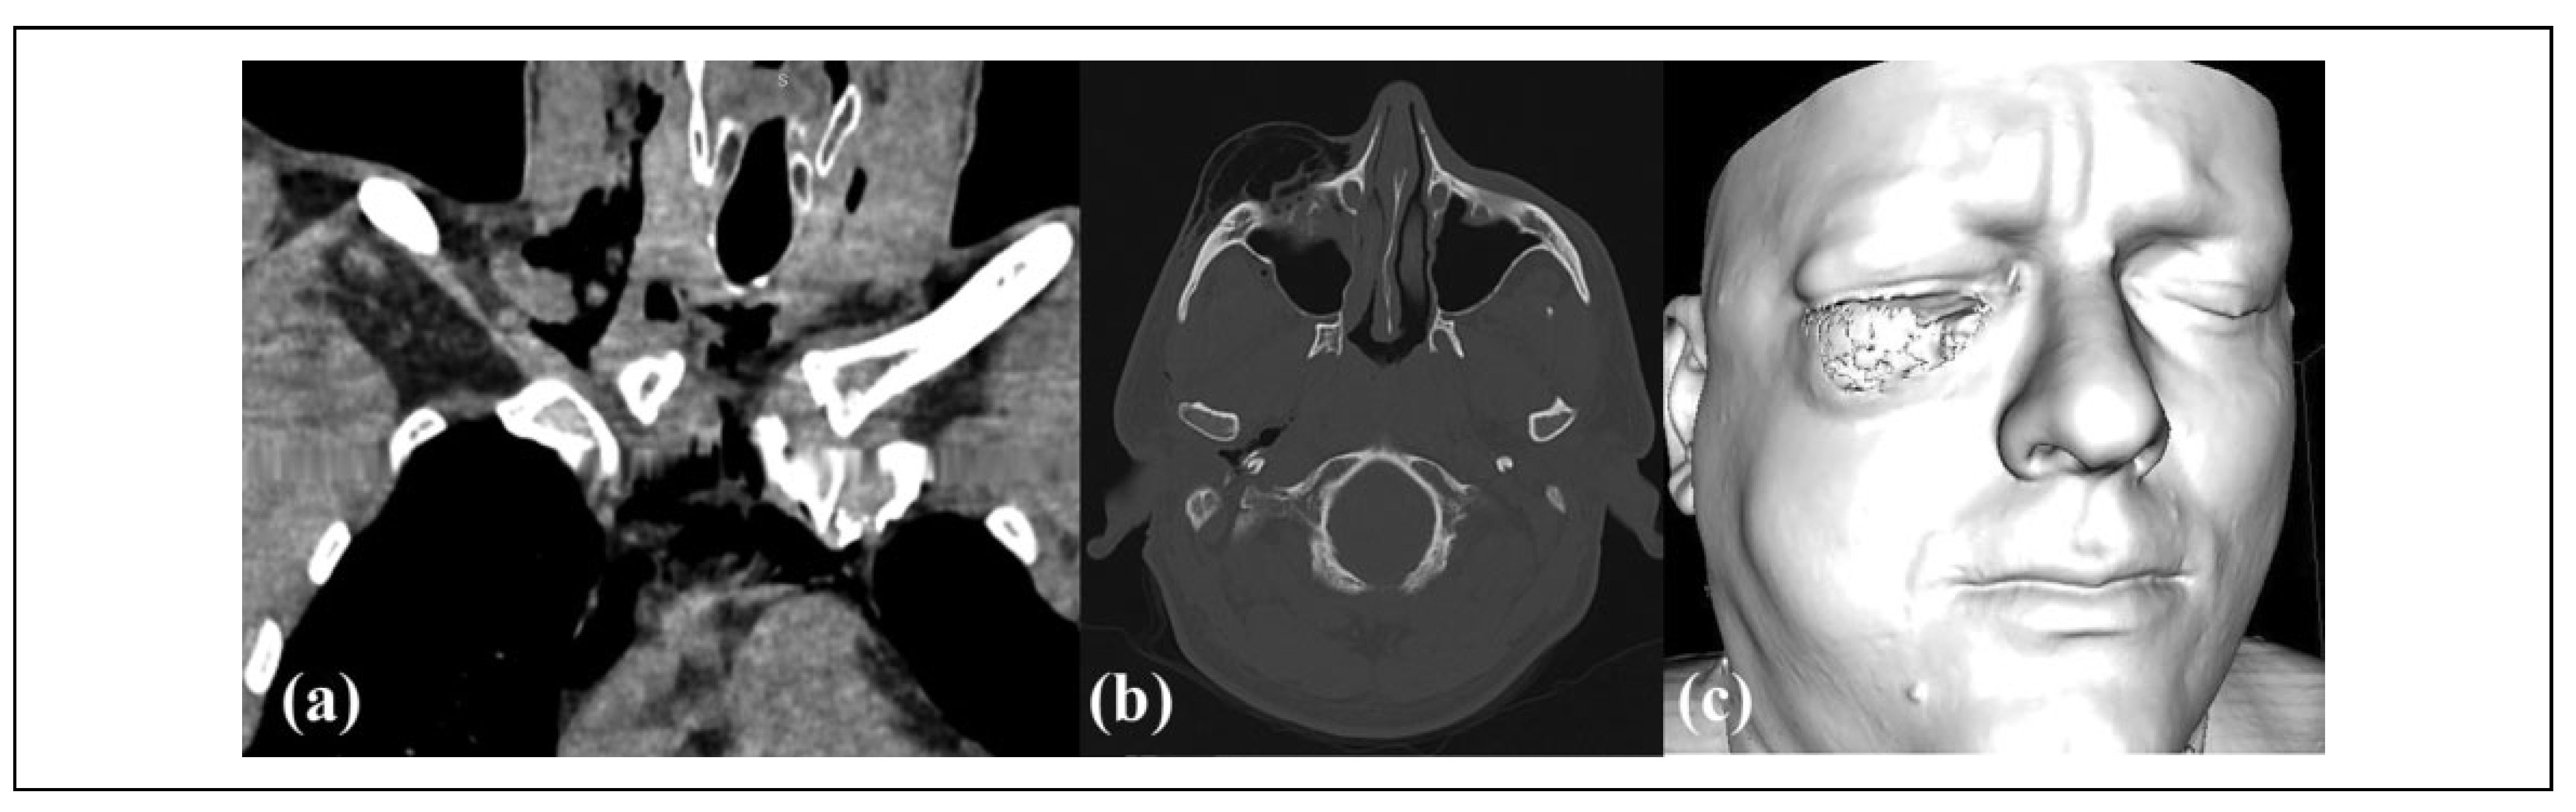

![]() |